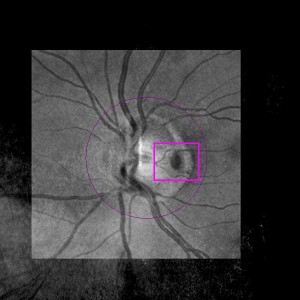

Grubenpapille (siehe Anmerkung)

Papillengrube (аббревиатура: Grube)